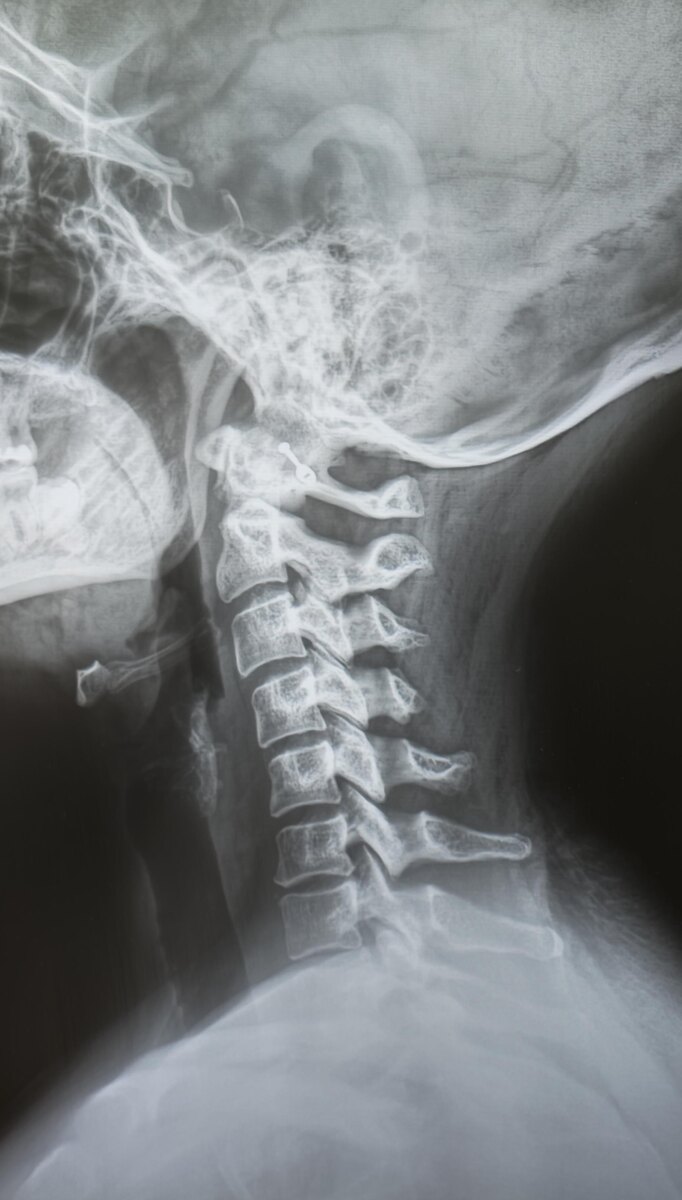

На днях просматриваю снимки шейного отдела позвоночника молодой пациентки, направлена с диагнозом-цервикалгия(боль в шейном отделе позвоночника).

На снимках, кроме кифотической установки в шейном отделе позвоночника, незначительного неравномерного сужения межпозвонковых щелей и не выраженного заострения унковертебральных отростков, патологии не выявлено. Однако взгляд цепляется за турецкое седло.

При измерении размеров турецкого седла получаются показатели: глубина 13.9мм, передне-задний(сагиттальный)-20.4мм. Нормальные размеры турецкого седла у взрослого: cагиттальный размер (передне-задний) 10–15 мм. Глубина 8–12 мм.

Заключение: Начальные проявления остеохондроза шейного отдела позвоночника. Унковертебральный артроз. Кифотическая установка шейного отдела позвоночника. Увеличение размеров турецкого седла-признак аденомы гипофиза.

Рек-но: дообследование- МРТ головного мозга, конс. нейрохирурга.